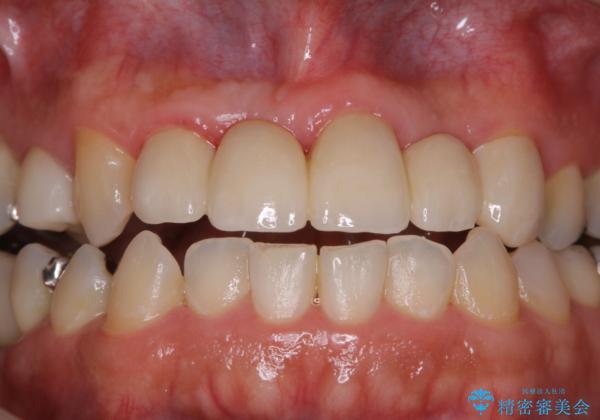

歯科衛生士によるPMTCでお口のケア

- 歯医者に来院することが久しぶりで、まずはクリーニングを希望とのことでした。コースや内容は、一番状態に合ったものでとのことだったため、PMTC60分コースを行いました。

審美的面だけではなく、歯周病や虫歯・口臭などのリスクを予防することができます。

汚れを除去することにより、症状の早期発見につながります。